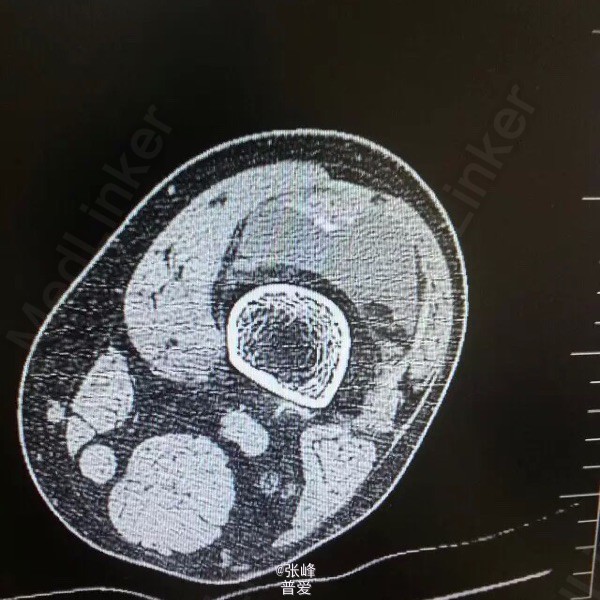

患者刘曙平,男,57岁。 左膝部肿痛、活动受限1天。 患者于昨天无明显诱因出现左膝肿胀,疼痛,伴活动受限。自行服药及局部外敷药治疗(具体不详),效果不明显,疼痛渐加重。为求进一步诊治,就诊我院,门诊了解病史、查体后以“左膝滑膜炎”收入院。 起病以来,精神一般,未进饮食,二便未解,体力尚好。 既往史:发现“高血压”4年,规律服用“倍他乐克”“波依定”,血压控制可;发现“痛风”20余年,目前症状控制一般。否认糖尿病、肝炎、结核等病史,否认药敏史。

诊断:左膝滑膜炎 诊疗计划:1.完善相关检查,如血尿常规分析、肝肾功能等。 2.对症治疗,观察左膝情况。 3.请示上级医师指导治疗。 者诉左膝部疼痛不适,无诉其他特殊不适,大小便正常。赵晶晶主治医师查房:患者根据既往病史、查体检查,目前考虑诊断左膝关节痛风性关节炎可能性大,暂以抗尿酸、对症支持及局部理疗,